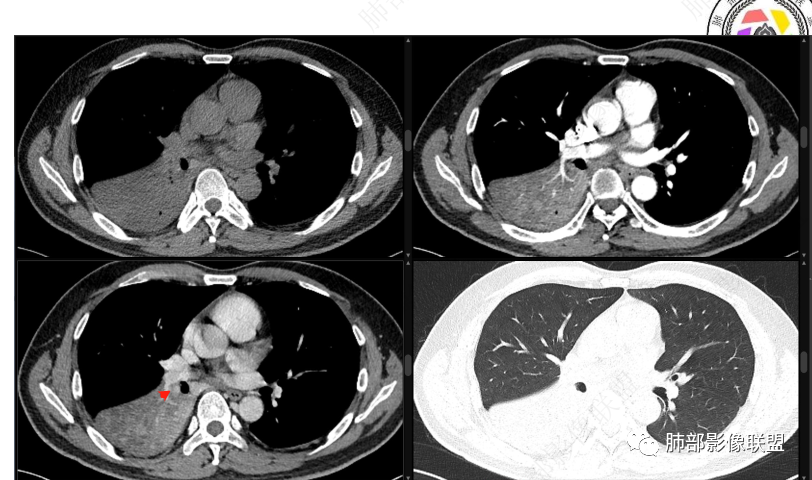

右下叶支气管狹窄,内见高密度强化结节,远端大片不张实变,实变内可见多发粘液拴,整体观察实变似有见缝就针的感觉,综和分析考虑粘液表皮样癌,其次考虑类癌

首先血管未见明显侵犯、移位,提示病灶:炎性;肿瘤:外朝内——含粘液类腺癌(肺门淋巴结转移),腔内肿瘤(鳞癌、腺癌、类癌、小细胞、粘液表皮等)

按这个特点周围要考虑肿瘤组织

腔内肿瘤,远端堵塞

如果重建确定在腔内,那就鉴别黏表

我觉得粘液表皮可能要放前面

腔内

按理类癌远端密度不会这么低

冠状位重建有钻缝的感觉

我再发一些图

这是源头

这些如果单纯不张肯定强化明显